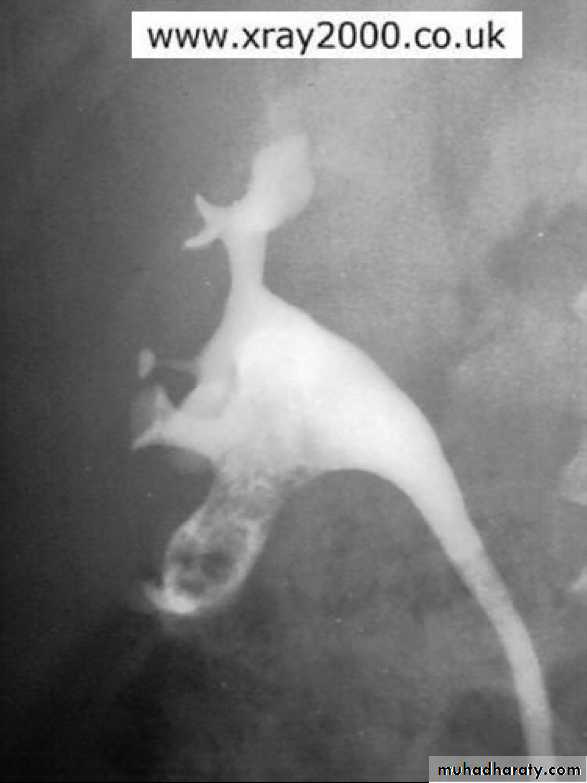

• IVU: Early stage –cobble stone Later filling defects due to graneulomatos papilloma Carcinoma is important complication Ureters : dilated and tortuousIn early stage hydroureter and hydronephrosis + refluxSPACE OCCUPING LESION